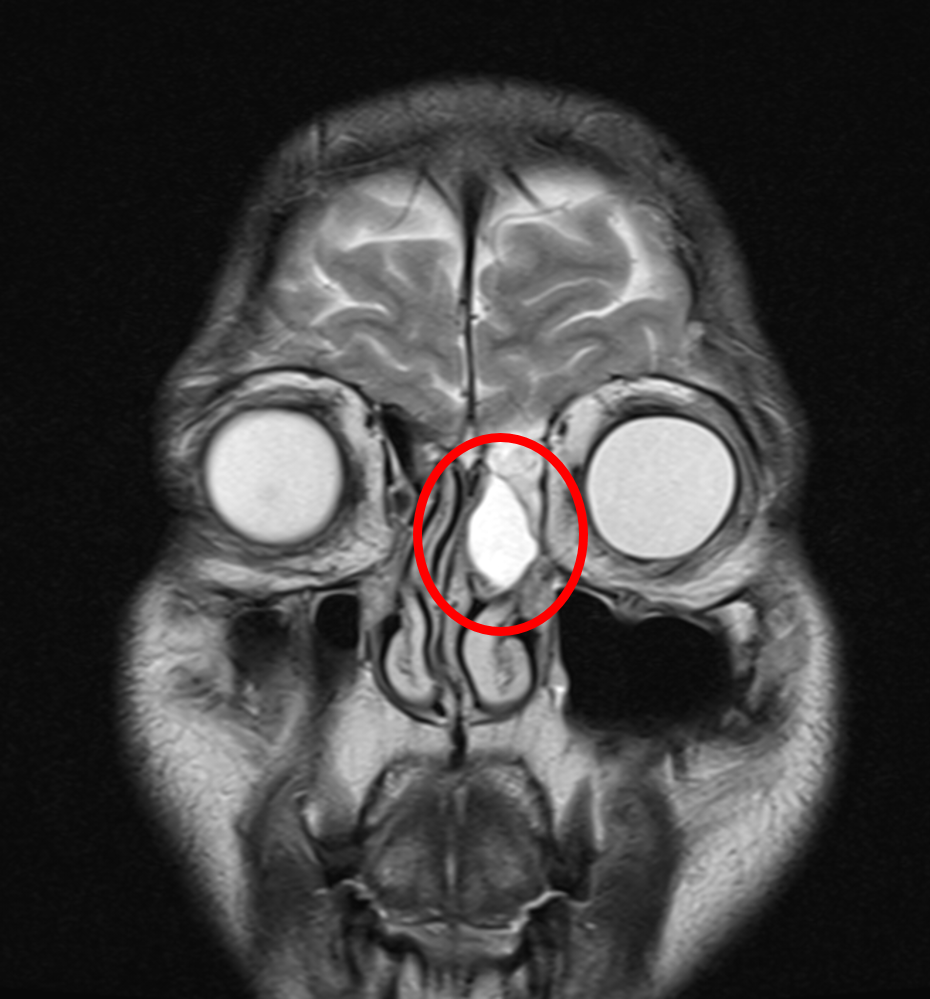

<안구와 뇌와 붙어 있는 혹>

항상 그렇다. 의사는 꼼꼼해야 한다. 점액낭종이 위로는 뇌바닥과 옆으로는 안구와 붙어 있어, 극히 드물긴 하지만, 잘못하면 눈이나 뇌에 손상이 올 수 있다. 또한 출혈이나 감염은 언제든지 생길 수도 있다. 내과 계열 의사라면, 검사 결과지와 차트, 그리고 쓴 약을 보면 어느 정도 성실함 여부를 알 수 있다. 하지만 외과 계열 의사는 수술을 직접 두 눈으로 보지 않는 한 알 수가 없다. 그것도 같은 의사라도 자기 파트가 아니면, 저 의사가 수술을 잘하는 건지 아닌 건지 모른다.